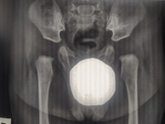

Девчат среди нас есть ортопеды?или те кто немного в этом шарит ?снимки сделаны в три(голубой)и в семь(серый)месяцев ,у нас только отсутствуют ядра окостенения или дисплазия (смещение ,вывих,подвывих)тоже есть ?завтра иду к врачу ,но все равно мучаюсь … Читать далее